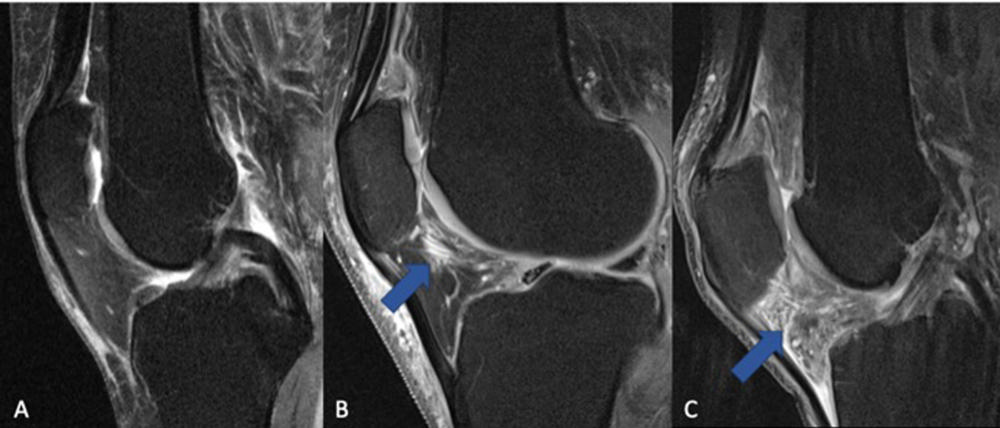

Figure 1. The fat pad adjacent to the kneecap (Hoffa's fat pad, infrapatellar fat pad) can change in signal on MRI when the knee is inflamed. (A) Normal knee without signs of inflammation. (B) Arrow pointing on a circumscribed area with higher signal (bright lines) in the area of the fat pad (normally dark), which is indicative of a beginning inflammatory reaction. (C) The whole fat pad has a higher signal (light grey color with white lines), which is a sign of progressive inflammation of the knee joint.